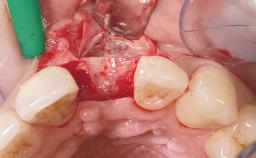

Late Placement of an Implant in a Maxillary Left Central Incisor Site

A 36-year-old female patient was referred for the replacement of the upper left central incisor (tooth 21), which had fractured. Although the tooth had been asymptomatic for many years, the crown began to loosen, at which time she presented to her dentist for an assessment. Teeth 21 and 22 had both been endodontically treated many years previously. She was a healthy individual and a non-smoker.

Bone Augmentation Horizontal|Staged

Augmentation Materials Xenogenous|Membrane

Soft Tissue Grafting Simultaneous